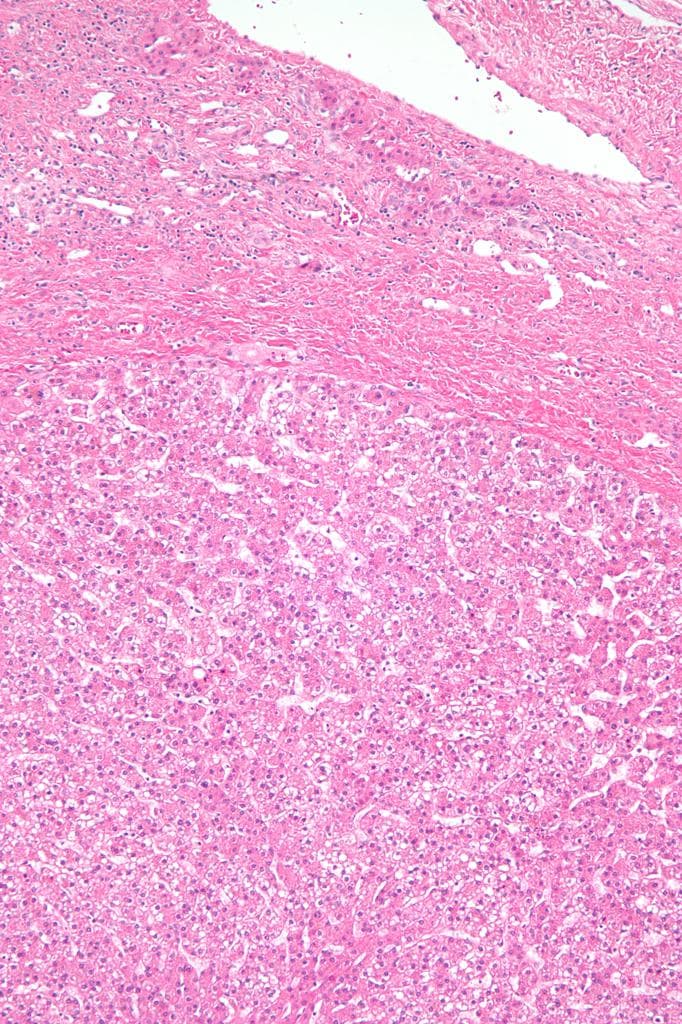

- Hình ảnh học phù hợp nhất với u tuyến gan có xuất huyết vào trong tổn thương (imaging features are most consistent with a hepatic adenoma with hemorrhage into it).

- Xuất huyết vào u tuyến gan (hemorrhage into hepatic adenoma)

- "Xuất huyết trong tổn thương u tuyến gan có thể biểu hiện tăng tín hiệu trên T1, giảm tín hiệu trên T2 và hạn chế khuếch tán."

Xuất huyết vào u tuyến gan là một biến chứng nghiêm trọng tiềm tàng của khối u gan lành tính, thường liên quan đến việc sử dụng thuốc tránh thai đường uống kéo dài. Hình ảnh học thường cho thấy tổn thương tăng tín hiệu trên T1, giảm tín hiệu trên T2 do methemoglobin trong xuất huyết bán cấp, với mức độ tăng quang thay đổi. Việc không thấy mỡ trên hình ảnh out-of-phase và không tăng quang đáng kể giúp phân biệt với các khối ác tính như ung thư biểu mô tế bào gan. Việc xác định chẩn đoán cần kết hợp lâm sàng, đặc biệt là tiền sử sử dụng hormone. Quản lý có thể bao gồm ngưng thuốc tránh thai, theo dõi định kỳ hoặc cắt bỏ ngoại khoa tùy theo kích thước, triệu chứng và nguy cơ vỡ.